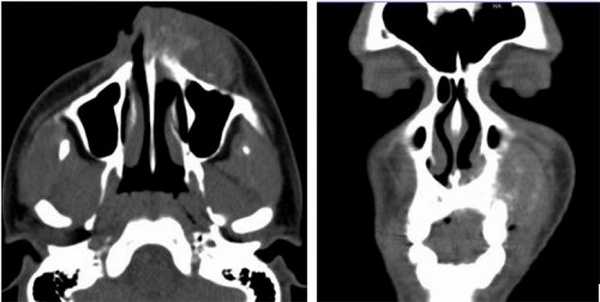

Пациент, муж, 19 лет обратился с жалобами на припухлость левой средней трети лица (Рис. 1).

Рис. 1. КТ свидетельствует об остеосаркоме, опухолевый инфильтрат происходит из передней стенки верхней челюсти слева, с вовлечением альвеолярной кости (остеолиз).